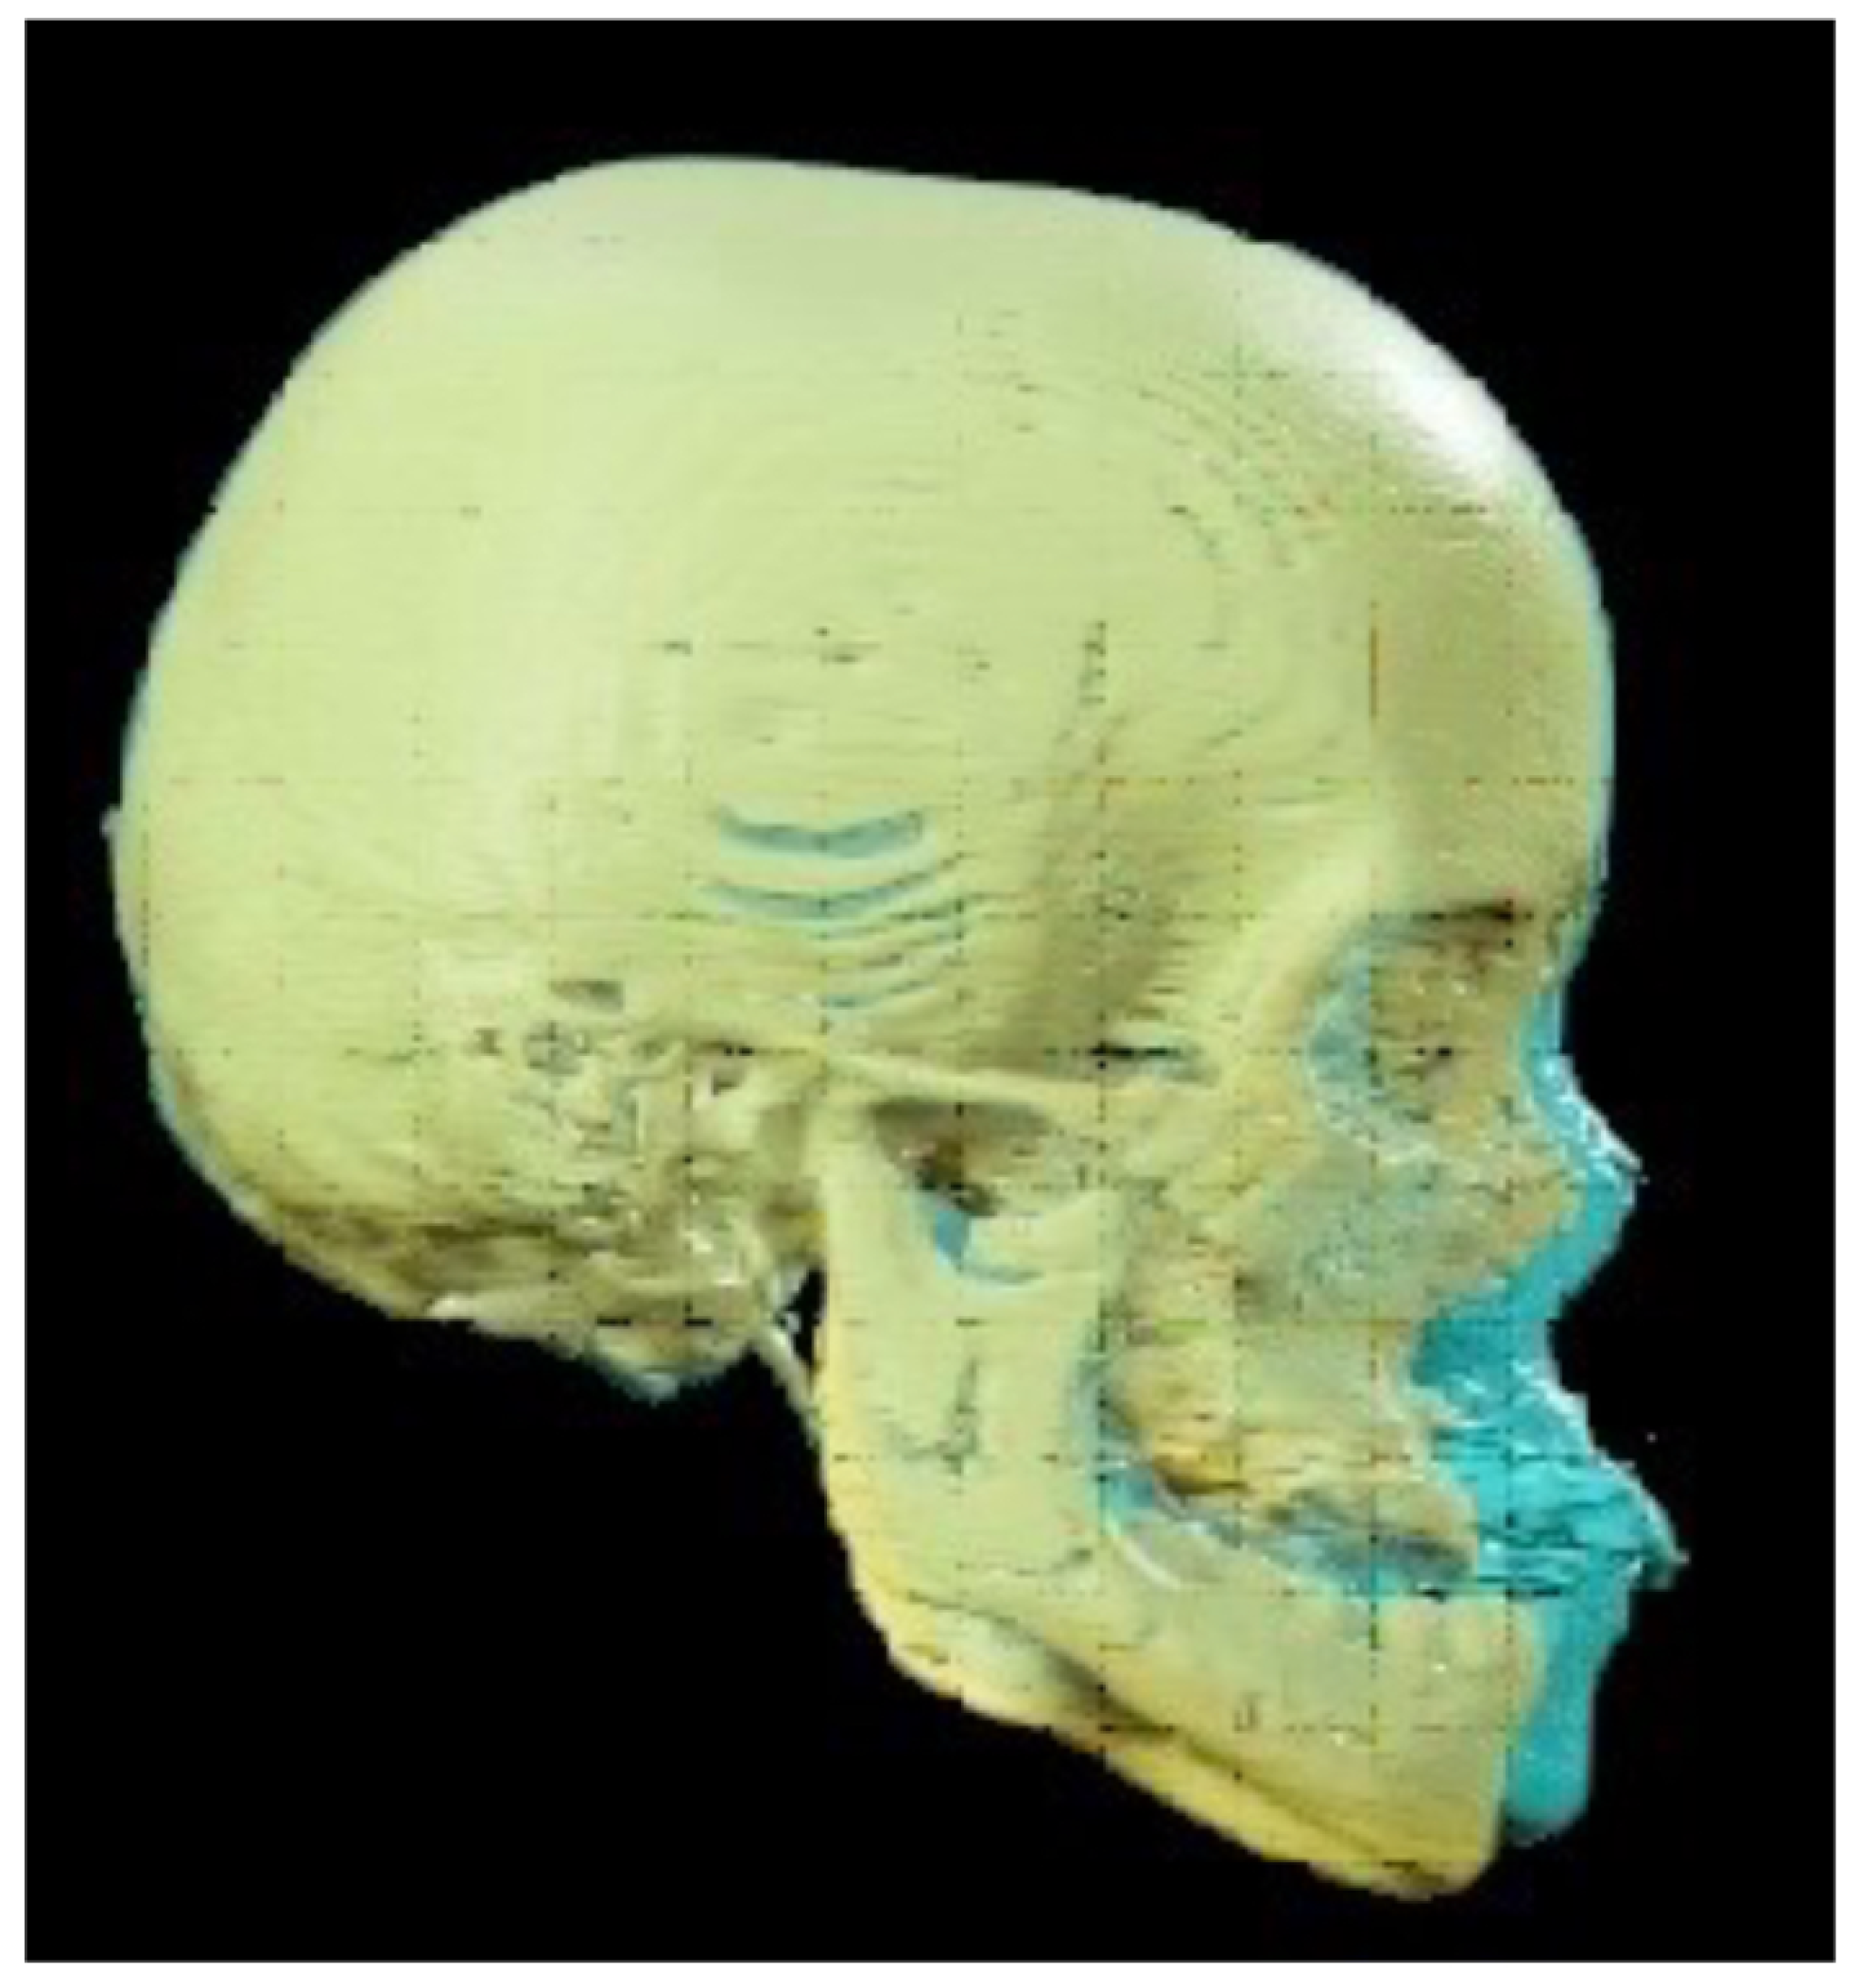

- Perform a CBCT to confirm the patency of the circum-maxillary sutures.

- Placement of a two-hinged rapid maxillary expander (RPE) and expansion of maxilla using a modified Alt-RAMEC (alternate rapid maxillary expansion and constriction) protocol [17,18,19] resulting in loosening of all circum-maxillary sutures without surgery. The treatment protocol consisted of 11 cycles with 7 days of expansion and 7 days of constriction, 1 mm per day, alternatively. After 11 weeks of alternate expansion–constriction, mild mobility of the whole maxilla was felt clinically.

- Placement of an external rigid distractor (RED) during a minor surgery under general anesthesia. The surgical procedure was performed with oro-tracheal intubation through an incision at the level of the upper vestibular fornix with skeletonization of the maxilla. The patency of the zygomatico-maxillary suture was noted. A plate and corresponding screws (Matrix Midface, DePuy Synthes, Raynham, MA, USA) were positioned on each side at the level of the maxillo-malar complex, and two plates, corresponding screws, and percutaneous pins (External Midface Distractor, DePuy Synthes, Raynham, MA, USA) were placed at the level of the lower orbital rim. Percutaneous traction wires were secured to the inferior plates and left protruding at the level of the naso-labial fold. After all intraoral wounds were sutured, the halo was positioned using four cranial screws per side (External Midface Distractor, DePuy Synthes, Raynham, MA, USA). The immediate post-operative period was organized in the Pediatric Intensive Care Unit. As ongoing NIV therapy was critical, the tractions of the RED were positioned in such a way as not to impede the placement of the NIV interface during night (Figure 5).

- Activation of the RED to allow advancement of the midface to overcorrect the dysmorphism. The activation started the day after surgery, 0.5 mm per day. After 4 weeks, the dislodgement of a bone anchorage plate was observed, necessitating an additional intervention to reposition it with a modification of its geometry. The activation continued for 5 additional weeks, for a total of 9 weeks, with an advancement reaching approximately 20 mm at the maxillary level.

- At the end of the distraction phase, after an additional stabilization period of 4 weeks, the RED was removed.

- Continuation of orthopedic–orthodontic treatment for approximately 9 months using intra-oral traction elastics, following the placement of orthodontic anchorage screws in the jaws under local anesthesia.